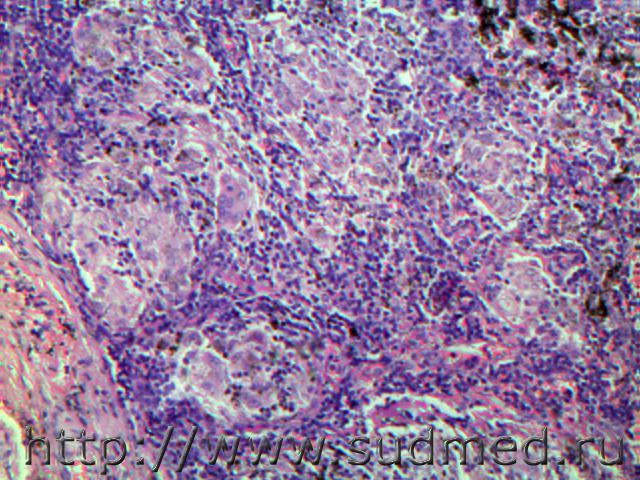

Злокачественная веретеноклеточная меланома с метастазами в головной мозг и легкие. 3и9 рисунок легкие, остальные ткань головного мозга с ММО.